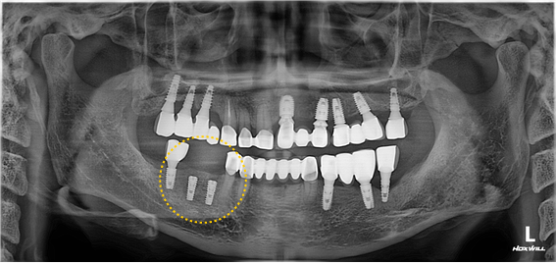

기존의 비싼 임플란트는 PFM이라는 재질로 되어있고,

참조은 임플란트는 지르코니아 소재로 되어있어 비교불가입니다.

더 중요한건 얼마나 정밀하게 만들어져 있는지를 보시면,

환자분도 바로 느끼셨듯이 너무 편안하다고 하시고, 정갈한 임플란트가 보이시나요?

맞춤형 지대주 및 지르코니아를 직접 생산하기에 좋은 재료, 우수한 퀄리티, 완벽한 A/S가 가능한 참조은치과입니다.